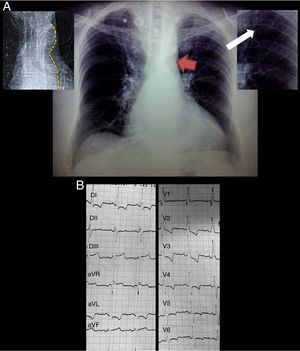

Physical exploration was remarkable for short stature, underdevelopment of lower extremities and laterally displaced apical impulse. Auscultation over the aortic area revealed a harsh meso-telesystolic crescendo-decrescendo murmur IV/VI radiating to carotids and apex with Gallavardin phenomenon. A loud systolic murmur was also heard over the left paravertebral area. Carotid pulse was parvus et tardus. Lower extremities pulses where markedly diminished. Blood pressure was 152/90mmHg in the upper extremities and 64/40mmHg in the lower extremities. Ankle brachial index was 0.42. Chest radiograph showed grade III cardiomegaly, radiographic data compatible with the “3” sign, inferior rib notching (Roesler sign) and calcified collateral vessels (Fig. 1A). The EKG demonstrated a sinus rhythm, complete right bundle branch block, left anterior fascicular block, biventricular hypertrophy and systolic overload of the left ventricle (Fig. 1B). Transthoracic echocardiography showed a calcific severely aortic stenosis with a mean gradient of 44mmHg, peak gradient of 73mmHg and a peak velocity of 4.2m/s. Left ventricular ejection fraction was 49%, there were no regional wall motion abnormalities. Transesophageal echocardiography confirmed a stenosed, functionally bicuspid aortic valve, aortic valve area was 0.6cm2 by planimetry (Fig. 2A and B). CT angiography revealed a markedly diminished descending aorta with a minimum diameter of 4mm measured 35mm after the origin of the left subclavian artery (Fig. 2C and D). Aortic root and ascending aorta size were normal (26 and 36mm respectively).

(A) Posteroanterior chest radiograph demonstrating situs solitus, levocardia, levoapex, left sided aortic arch, normal pulmonary blood flow and grade III cardiomegaly, additionally the “3” sign (red arrow), inferior rib notching (white arrow) and calcified collateral vessels (*). Top left panel delineating the descending aorta contour from the same patient in the thoracic scout CT image. Top right panel is a zoom of the inferior rib notching. (B) Standard 12 lead EKG demonstrating a sinus rhythm, complete right bundle branch block, left anterior fascicular block, biventricular hypertrophy and systolic overload of the left ventricle.